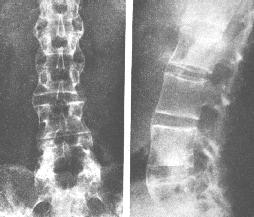

强直性脊柱炎

AS ①晚期 ②重度 病史:5年+

治疗后骶髂关节疼痛消失,腰椎前屈、背伸侧弯活动自如,膝关节无压痛感,复查血沉、C反应蛋白、等各项检查均已达到临床康复的标准。